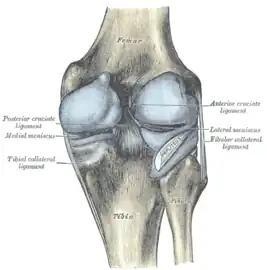

Ligaments

The ligaments surrounding the knee joint offer stability by limiting movements and, together with the menisci and several bursae, protect the articular capsule.[19]

Intracapsular

The knee is stabilized by a pair of cruciate ligaments. These ligaments are both extrasynovial, intracapsular ligaments.[20] The anterior cruciate ligament (ACL) stretches from the lateral condyle of femur to the anterior intercondylar area.[13] The ACL prevents the tibia from being pushed too far anterior relative to the femur.[13] It is often torn during twisting or bending of the knee.[21] The posterior cruciate ligament (PCL) stretches from medial condyle of femur to the posterior intercondylar area. This ligament prevents posterior displacement of the tibia relative to the femur.[13] Injury to this ligament is uncommon but can occur as a direct result of forced trauma to the ligament.

The transverse ligament stretches from the lateral meniscus to the medial meniscus. It passes in front of the menisci. It is divided into several strips in 10% of cases.[10]: 208 The two menisci are attached to each other anteriorly by the ligament.[22] The posterior (of Wrisberg) and anterior meniscofemoral ligaments (of Humphrey) stretch from the posterior horn of the lateral meniscus to the medial femoral condyle. They pass anterior and posterior to the posterior cruciate ligament respectively.[13][10]: 208 The meniscotibial ligaments (or "coronary") stretches from inferior edges of the menisci to the periphery of the tibial plateaus.

Illustrations

Cruciate ligaments

Left knee-joint from behind, showing interior ligaments.